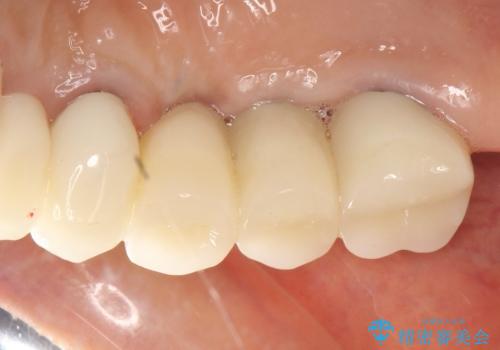

インプラントの種類:Bicon

かぶせ物の種類:PFZ